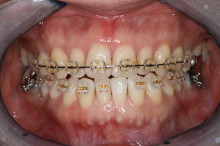

矯正

まず、下の前歯を1本抜きました。

次に、ブラケットと呼ばれる矯正装置を歯の表面につけて

下の前歯を抜いてできた隙間に隣の歯を移動させていきます。